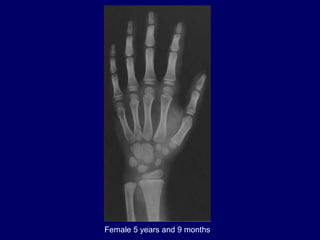

Female 5 years and 9 months